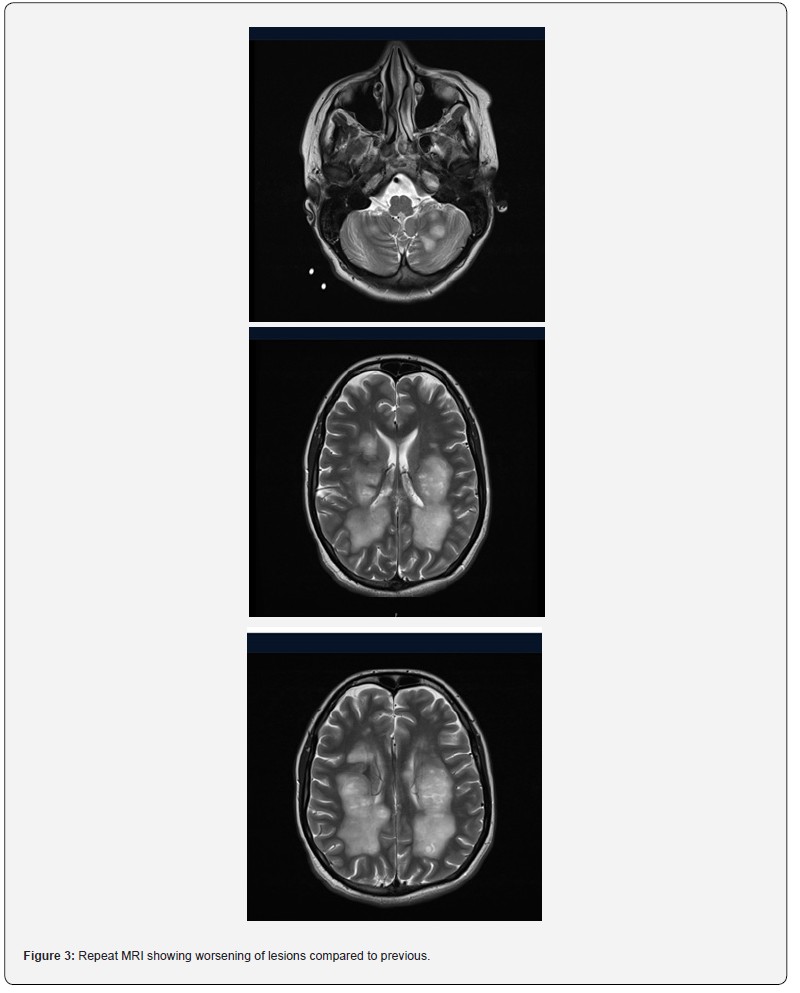

A repeat MRI showed extensive areas of signal abnormality, which appeared swollen and extended from the subcortical white matter along the corona radiata into the posterior limb of internal capsule, cerebral peduncles, cerebellar white matter, cerebellar peduncle and central medulla (Figure 2). A conclusion of aggressive inflammatory or demyelinating or tumefactive process was made with differentials of ADEM, post viral, acute necrotising encephalopathy.

To determine the cause, a whole panel of investigations were sent that included tumor markers, autoimmune panels, paraneoplastic screen, specific antibody screen as well as an extended viral panel and a porphyria screen (Table 1), but all were negative. EEG showed non-specific encephalopathic changes without evidence of seizure activity. Meanwhile, she was started on plasma exchange. No improvement was observed even after 3 cycles. A neuroinflammatory multidisciplinary team meeting concluded that there was clinical and radiological deterioration despite steroids, IVIg and plasma exchange; and a trial of rituximab is warranted. Despite receiving 2 doses of rituximab, her progress was very slow. After around 3 months of total hospital stay, she was discharged on long term steroid and antiepileptic therapy. She still has significant disability and continues to require assistance for activities of daily living (Figure 3).